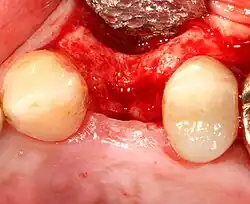

- Soft tissue reflection: An incision is made over the crest of bone, splitting the thicker attached gingiva roughly in half so that the final implant will have a thick band of tissue around it. The edges of tissue, each referred to as a flap, are pushed back to expose the bone. Flapless surgery is an alternate technique, where a small punch of tissue (the diameter of the implant) is removed for implant placement rather than raising flaps.

Additional procedures to augment deficient bone in implant site

For an implant to osseointegrate, it needs to be surrounded by a healthy quantity of bone. In order for it to survive long-term, it needs to have a thick healthy soft tissue (gingiva) envelope around it. It is common for either the bone or soft tissue to be so deficient that the surgeon needs to reconstruct it either before or during implant placement.[31]: 1084 All techniques of augmenting the alveolar bone in preparation for implant placement are invasive and associated with a degree of morbidity.[40]

Soft tissue (gingiva) reconstruction

The gingiva surrounding a tooth has a 2–3 mm band of bright pink, very strong attached mucosa, then a darker, larger area of unattached mucosa that folds into the cheeks. When replacing a tooth with an implant, a band of strong, attached gingiva is needed to keep the implant healthy in the long-term. This is especially important with implants because the blood supply is more precarious in the gingiva surrounding an implant, and is theoretically more susceptible to injury because of a longer attachment to the implant than on a tooth (a longer biologic width).[45]: 629–633